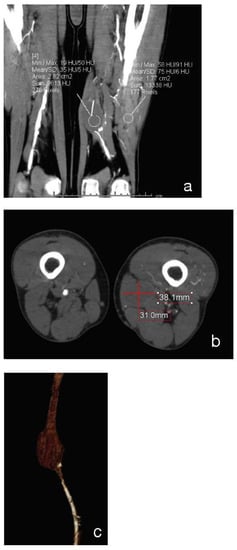

On clinical examination, he had leg pain and swelling. There was no presence of motor or sensory deficits. Rutherford classification Grade II, Category 4, with AP < 38 mmHg. The angio-CT scan of the abdomen and lower limbs revealed that the iliac artery, common femoral artery and deep femoral artery of the left side were atheromasic but patent, whereas the FP bypass was completely occluded (Figure 1). At distal anastomosis, a PA which measured 31 × 38 × 55 mm was present (Figure 2a–c). The left popliteal artery was revascularized by collateral vessels coming from the deep femoral artery. On the right side, there was regular patency of the leg arteries.

Figure 2. Coronal (a), Axial (b) and 3D-reconstruction (c) show the occlusion of distal anastomotic PA.